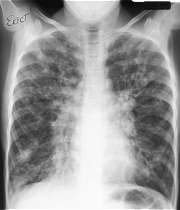

La fibrosis quística es un trastorno multisistémico que causa la formación y acumulación de un moco espeso, que afecta principalmente a los pulmones, intestinos, páncreas e hígado, que causa dificultad para respirar y puede derivar en infecciones pulmonares crónicas, problemas digestivos y otras complicaciones como diabetes.